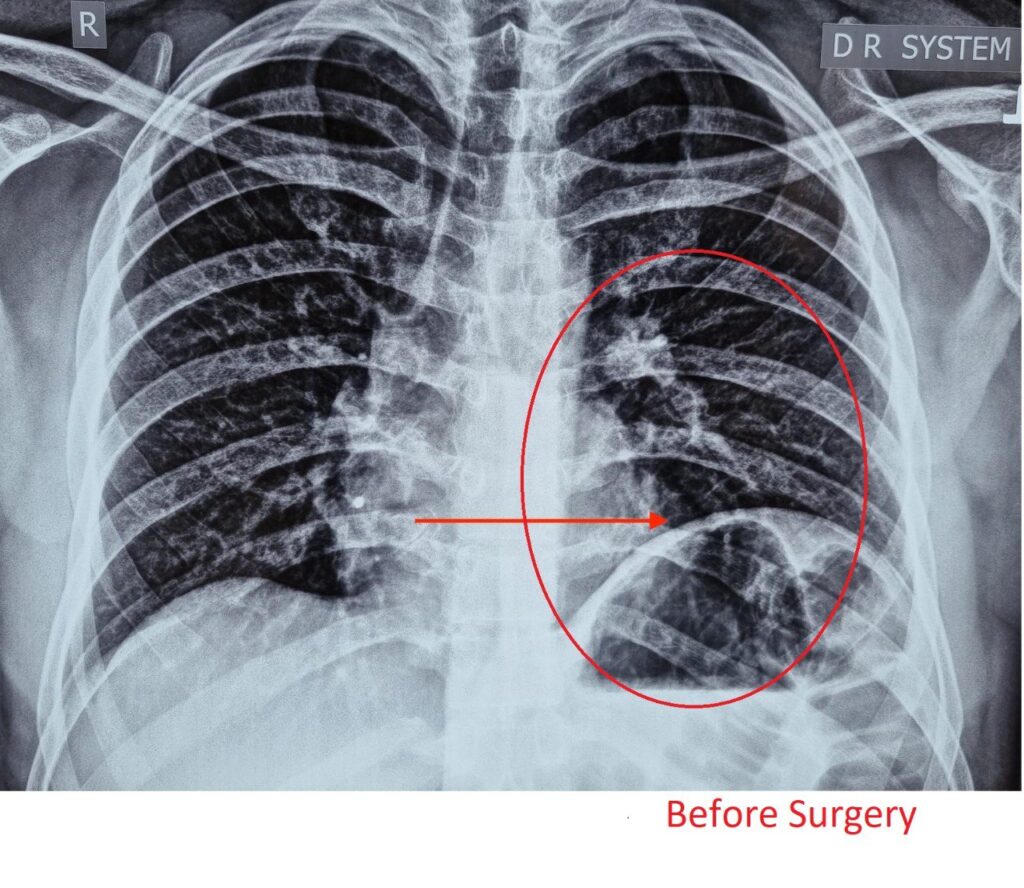

रामसिंगला असलेला हा आजार व त्यावरील उपचाराविषयी बोलताना झायनोव्हा शाल्बी हॉस्पिटलचे बॅरिएट्रिक सल्लागार आणि जीआय सर्जन डॉ. जयदीप पालेप सांगतात, रामसिंगला असलेल्या या आजाराचे नाव इवेन्ट्रेशन ऑफ डायफ्राम असे असून हे एक दुर्मिळ वैद्यकीय स्थिती आहे.डायफ्राम म्हणजे छातीच्या पोकळी आणि उदरपोकळी दरम्यान स्नायूंचा सेप्टम आहे.जो श्वासोच्छवासाचा मुख्य स्नायू आहे आणि उदर आणि छातीची पोकळी वेगळे करतो. परंतु या केसमध्ये डायफ्रामला भेदून पोट आणि कोलन सारख्या पोटातील सामग्री छातीमध्ये सरकली होती त्यामुळे रामसिंगला उलट्या होणे, धाप लागणे अशी लक्षणे वांरवार दिसत होती.

हा आजार जन्मजात असून जर त्यावेळी उपचार केले असते तर त्याला कोणताही त्रास झाला नसता परंतु हा आजार वयाच्या २९ व्या वर्षापर्यंत दुर्लक्षित राहिला व या आजारावर जर उपचार झाले नाही तर फुफ्फुसाचे कायमचे नुकसान होऊ शकते. यामध्ये आम्ही सिटी स्कॅन व इतर वैद्यकीय चाचण्या करून त्याचे योग्य निदान झाले व त्यावर आम्ही लॅप्रोस्कॉपीक शस्त्रक्रिया करून त्याचे प्राण वाचविले.

ओटीपोटावर फक्त ४ लहान कट होते आणि शस्त्रक्रियेनंतर रामसिंगच्या श्वासोच्छवासात त्वरित सुधारणा झाली शस्त्रक्रियेनंतर केलेल्या छातीच्या एक्स-रेमध्ये डायाफ्राम सामान्य स्थितीत दिसून आला. शस्त्रक्रियेनंतर रामसिंगला ४८ तासांत त्यांना डिस्चार्ज देण्यात आला.”